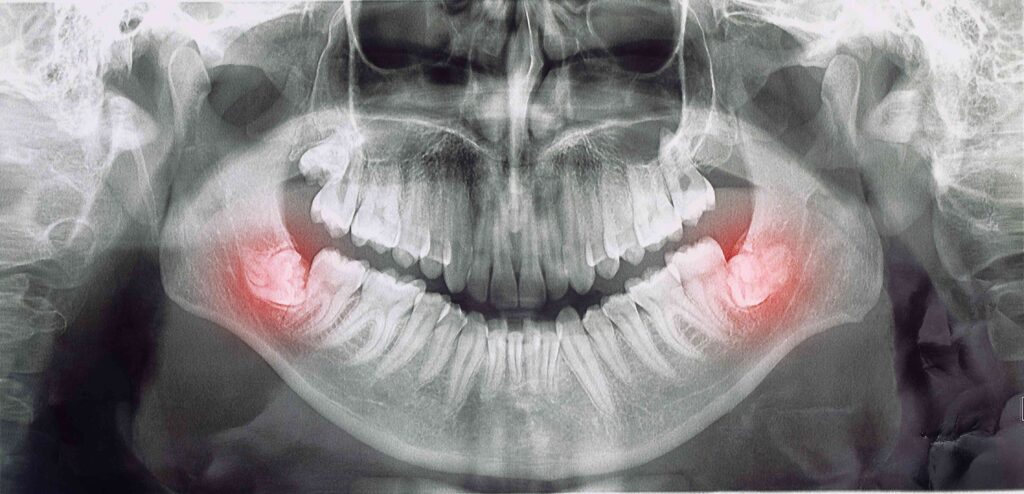

Wisdom teeth don’t only need to be removed if they are causing pain. There are a variety of reasons why your dentist may recommend the procedure. This could include inflammation, bleeding gums, damage to surrounding teeth, or not having enough room to accommodate them. Some people never need to get their wisdom teeth extracted because their jaws are large enough to equip them without overcrowding. Your dental will let you know if they think you’d benefit from the procedure.

As you get older, the roots of your wisdom teeth become more deeply embedded and can result in a more complex procedure, so wisdom tooth extractions are typically recommended during late adolescence and early adulthood. However, it is never too late to have your wisdom teeth removed. Older adults often need their third molars removed because they become impacted or infected. This can cause intense pain and pressure that can damage the neighboring teeth. Ultimately, having your wisdom teeth removed now at the recommendation of your dentist can prevent possible complications later in life.

The older you are, the more risks are associated with the procedure. As the roots of the teeth grow closer to the nerve, there is a very slight chance that you could lose some degree of feeling in the area when you have them removed. Older patients also generally require a longer recovery time. You may need to take a week to fully recover as opposed to a few days for younger patients. Your oral surgeon will provide you with all of the aftercare instructions that you need to make the healing process as comfortable and quick as possible.